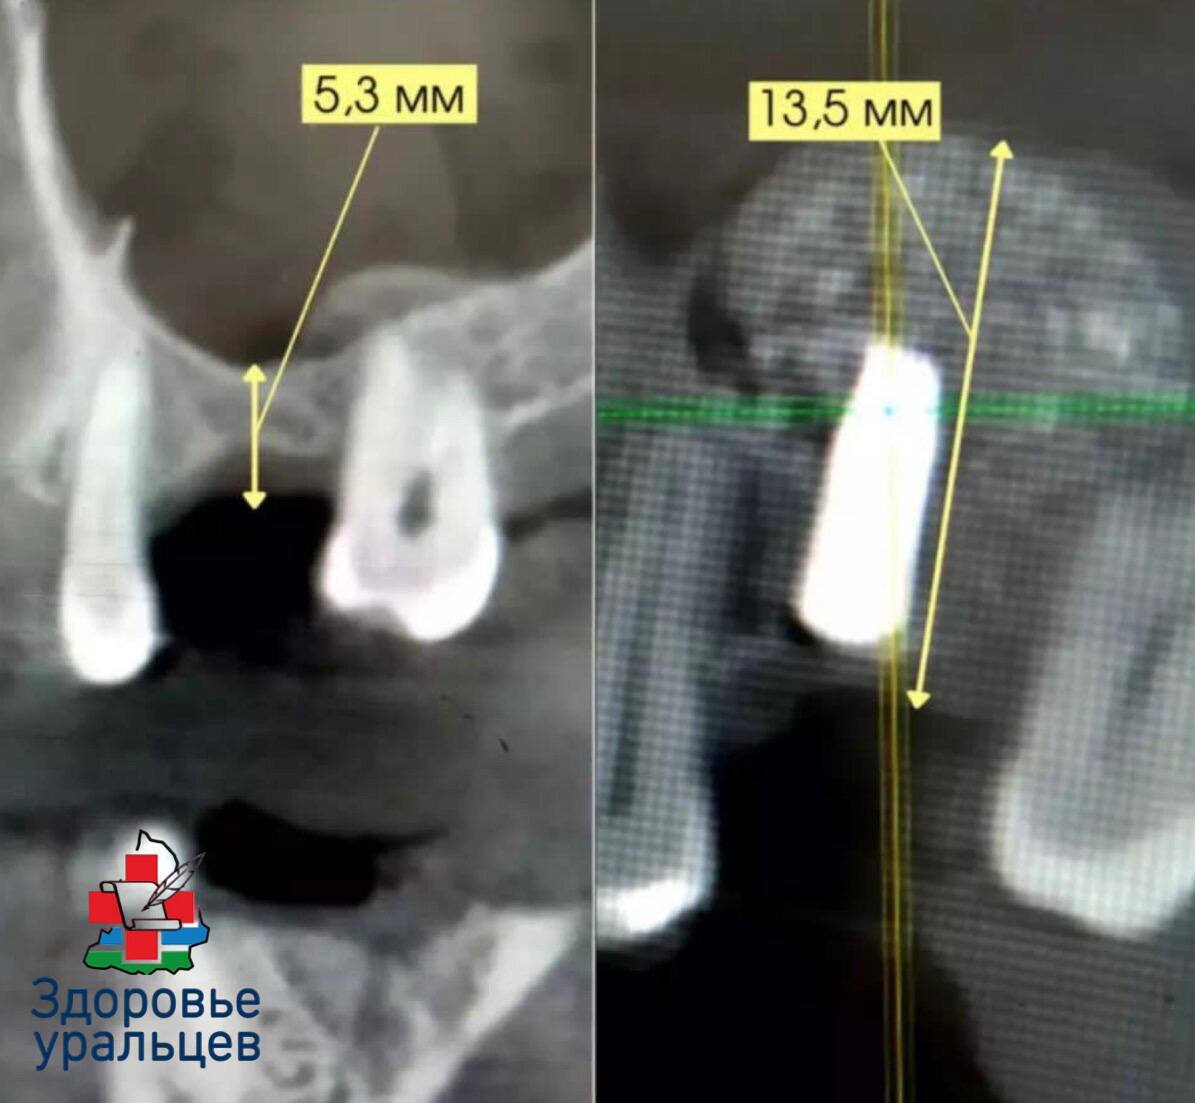

Операция назначается в случае, если костная масса верхней челюсти в области гайморовых пазух атрофировалась, стала тонкой из-за потери зубов, травм, заболеваний дёсен и других патологий, а толщина кости для установки имплантата не может быть менее 11 миллиметров. Синус-лифтинг позволяет восстановить требуемый объём костной ткани.

На этапе обследования пациента челюстно-лицевые хирурги Демидовской больницы проводят осмотр, выполняют компьютерную томографию для определения толщины кости верхней челюсти, изучают строение, расположение гайморовой пазухи. После этого принимается решение о проведении операции и определяется метод вмешательства — открытый или закрытый, в зависимости от размера недостающей костной ткани.